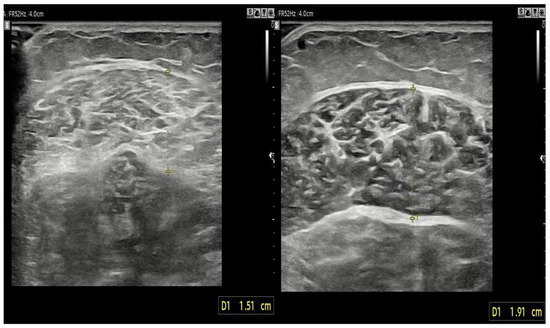

2.3.4. Stiffness and Thickness of the Muscle